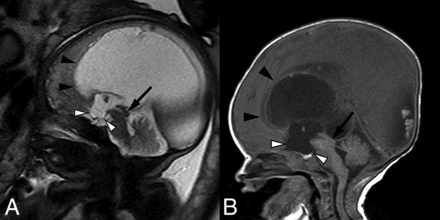

Fetal MR imaging of a 30-week fetus (A) and postnatal MR imaging correlation (B) of prenatally diagnosed aqueductal stenosis with tectal thickening and loss of intercollicular sulcus (arrows). There is subtle early prominence of the supraoptic recess of the third ventricle on fetal MR imaging (white arrowhead), which progressed to more obvious dilation of both supraoptic and infundibular recesses on postnatal imaging (white arrowheads). Note also the presence of a superiorly bowed and thinned corpus callosum (black arrowheads).

A single-shot fast spin-echo sequence in the axial planes (A and B) through the fetal head in a 23-week fetus and postnatal axial T2-weighted sequence (C and D) demonstrate asymmetric lateral ventriculomegaly with focal parenchymal disruption resulting in a posterior ventricular diverticulum (black arrowheads). Note also perforation of the septum pellucidum in A and C (arrow). Within the posterior fossa (B and D), there are a small transverse cerebellar diameter, absence of the cerebellar vermis, midline fusion of cerebellar folia, and a convex posterior cerebellar contour (white arrowheads), compatible with rhombencephalosynapsis.